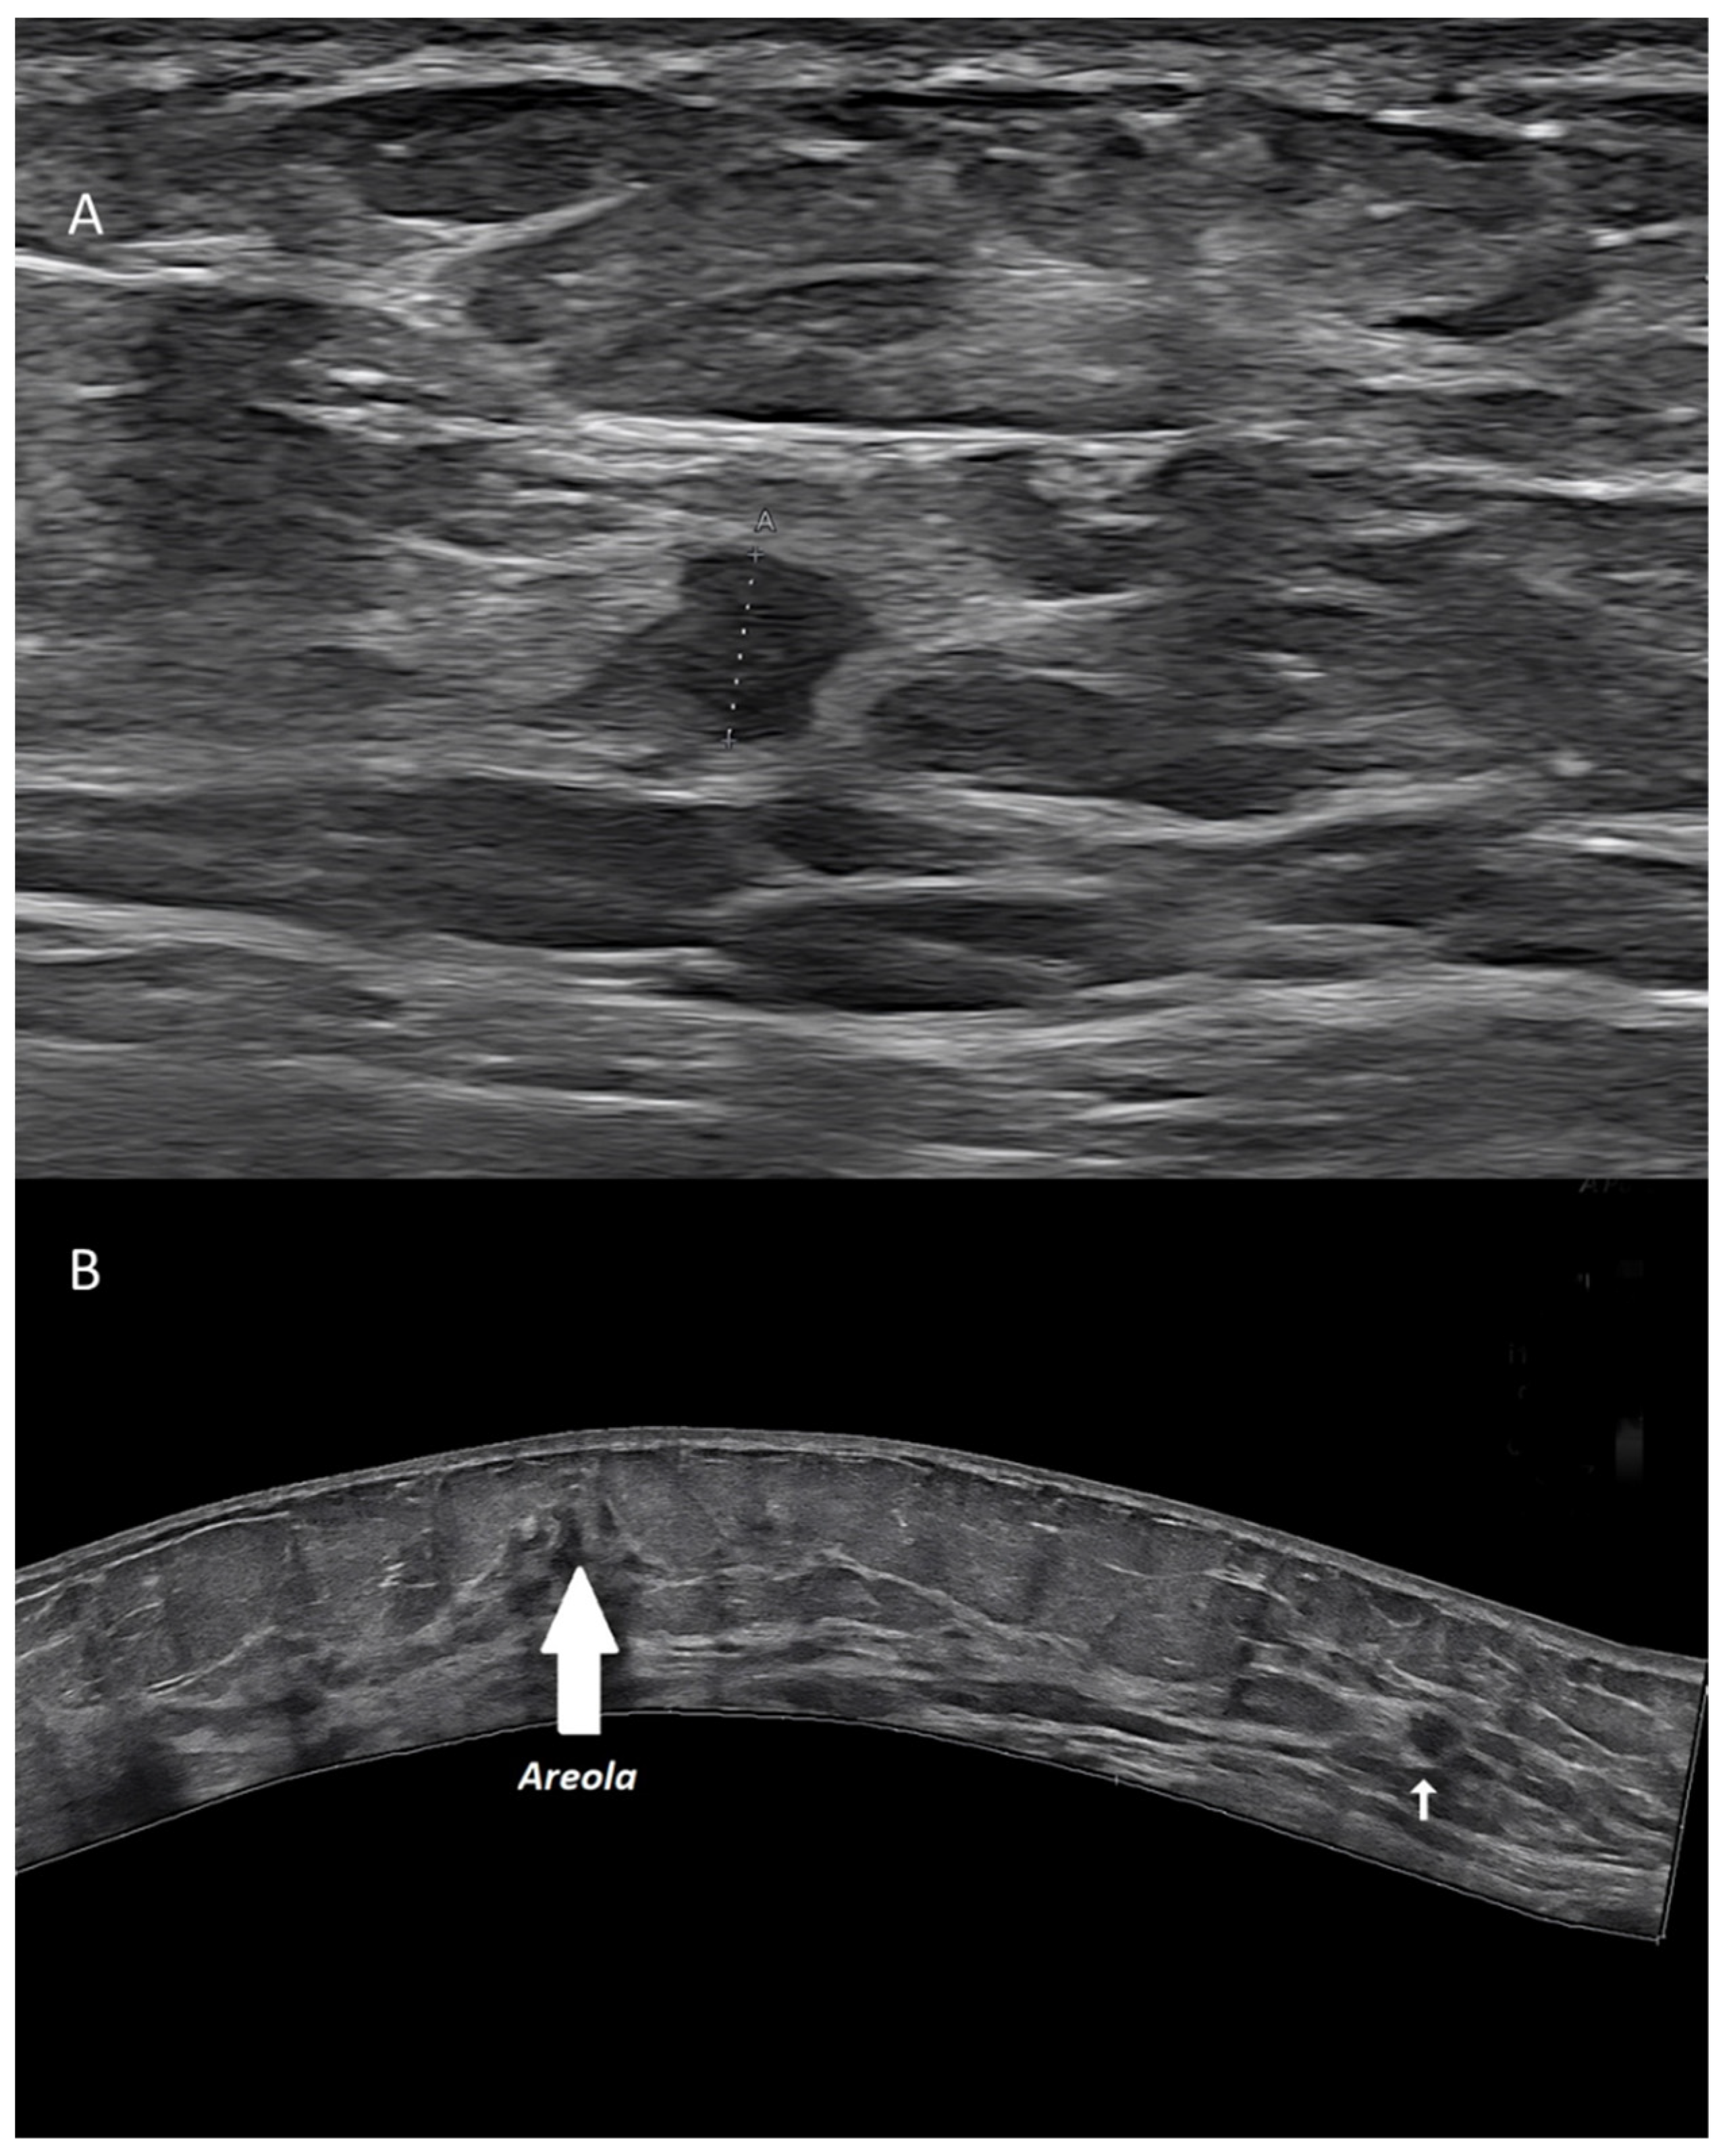

Figure 3. Invasive ductal carcinoma of the breast. (A) US scan showing a 4-mm nodule (calipers). (B) Extended FOV scan displaying the nodule (arrow) within the whole breast.